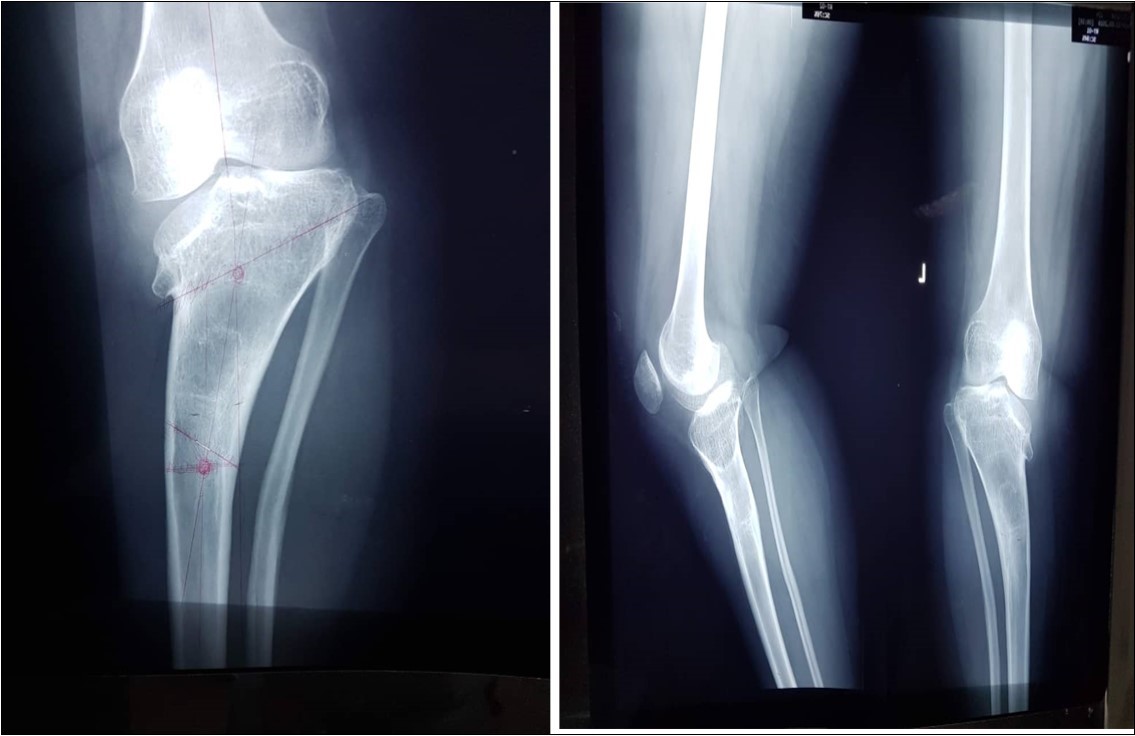

Physical examination revealed a boy who looked well with bilateral tibia vara, procurvatum and internal tibial torsion, Figure 3. There was a palpable posteromedial metaphyseal beak. There were no abnormalities detected in other systems.

Figure 3.Pre-operative photograph of the patient, standing I, and lying, II.

There was a varus angle of 70 degrees as measured by a goniometer when weight-bearing. The range of motion in both knees was 0-100 degrees. X-ray confirmed a Langenskiold stage VI tibia vara on either side, Figure 4.

Figure 4.Fig showing pro-operative radiograph of the left tibia and fibula